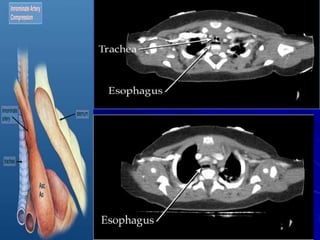

PULMONARY ARTERY SLING

A pulmonary artery sling is a rare vascular

anomaly in which the left pulmonary artery

originates from the right pulmonary artery

and encircles the right mainstem bronchus

and distal trachea before coursing anterior

to the esophagus and descending aorta to

enter the hilum of the left lung

A chest radiograph may show

unilateral hyperaeration of the right

lung field.

A barium esophagogram shows

anterior compression of the

esophagus on the lateral views.

Both CT and MRI will show the left

pulmonary artery originating from the

right pulmonary artery, encircling the

trachea, and coursing to the hilum of

the left lung .